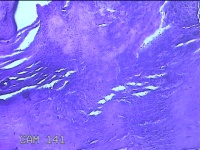

右侧拇指掌侧结节

性别

女

年龄

25岁

临床诊断

皮下结节

一般病史

发现右侧拇指结节2个月余。

标本名称

大体所见

灰白粉红色带皮肤样结节1.5x0.5x0.3cm一个,表面糜烂,切开结节呈实性,切面灰白粉红色,质软。